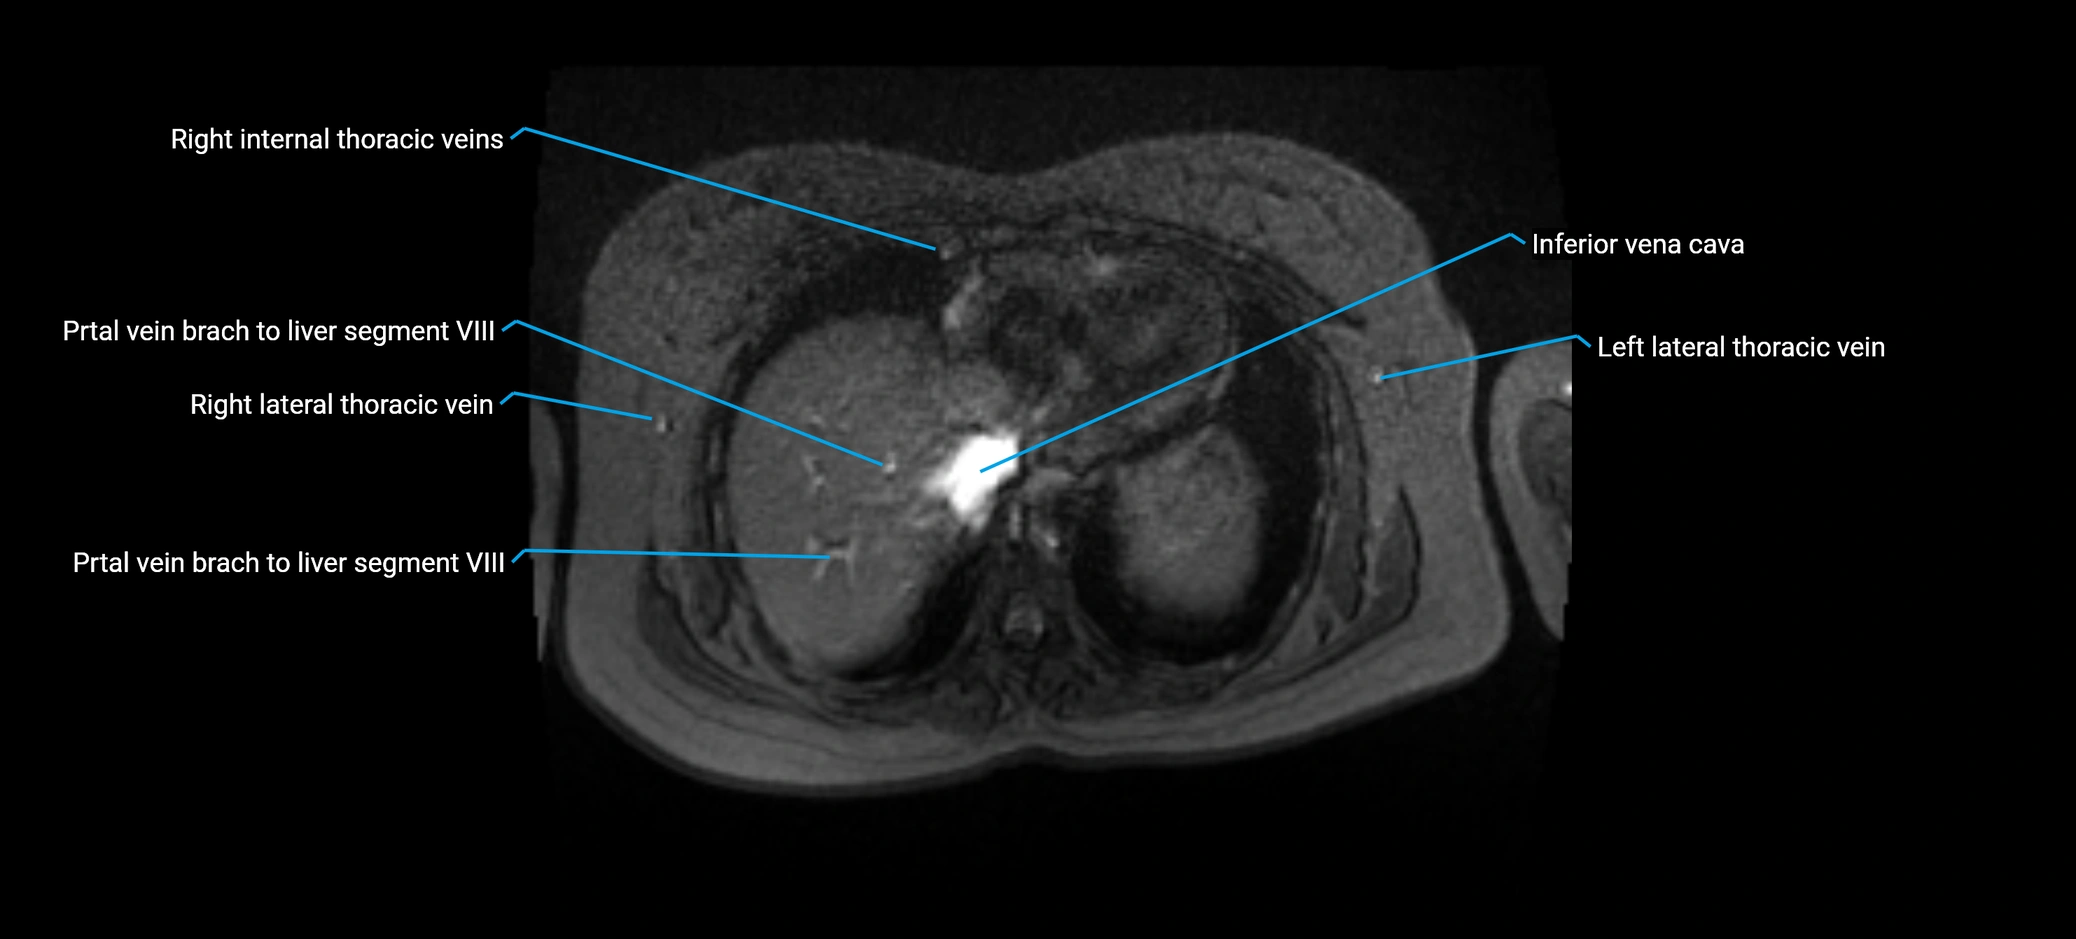

MRV TOF (Time-of-Flight MR Venography):

• Appears as a bright, high-signal vascular channel representing flowing blood

• Clearly shows branching pattern of right portal vein into anterior and posterior branches

• Best in coronal or axial reconstructions for segmental mapping

• No need for contrast, relies on flow-related enhancement

• Clearly delineates branching into segments V and VIII

• Best sequence for evaluating patency, caliber, and anatomic variants

MRI image

image